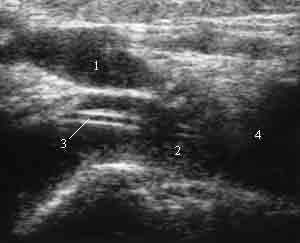

Анатомия внутренней яремной вены: КТ изображения